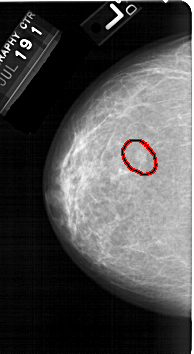

FILE: A_1323_1.LEFT_MLO.OVERLAY

TOTAL_ABNORMALITIES 1

ABNORMALITY 1

LESION_TYPE MASS SHAPE OVAL MARGINS OBSCURED-ILL_DEFINED

ASSESSMENT 4

SUBTLETY 2

PATHOLOGY BENIGN

TOTAL_OUTLINES 1

BOUNDARY